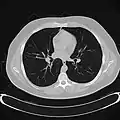

Blood supply

3D rendering of a high-resolution CT scan of the thorax. The anterior thoracic wall, the airways and the pulmonary vessels anterior to the root of the lung have been digitally removed in order to visualise the different levels of the pulmonary circulation.

The lungs have a dual blood supply provided by a bronchial and a pulmonary circulation.[4] The bronchial circulation supplies oxygenated blood to the airways of the lungs, through the bronchial arteries that leave the aorta. There are usually three arteries, two to the left lung and one to the right, and they branch alongside the bronchi and bronchioles.[32] The pulmonary circulation carries deoxygenated blood from the heart to the lungs and returns the oxygenated blood to the heart to supply the rest of the body.[32]